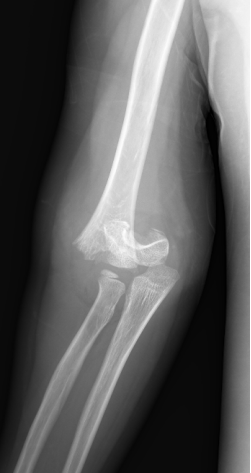

小玉(化名):女、9岁、3年前吊单杠时不慎摔伤致左肱骨髁上骨折,在当地医院行保守治疗。(下图为患儿X线片)

受伤当时X线片

手法复位后X线片

伤后一月后X线片

受伤后3年明显肘内翻畸形